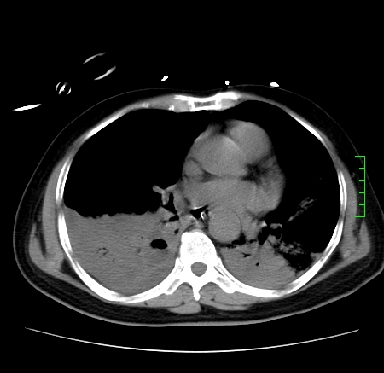

icu病人,几天都没明确诊断。m,76y,咳嗽、咳痰1周,伴气促,右胸痛入院,pe:t38.3c p135 r25 bp135/85。双肺可闻及大量湿罗音,心、腹未见明显异常。诊断:1心衰?2肺部感染?3冠心病?

11号ct

1)两肺感染性病变(右肺下叶肺脓肿可能)。2)双侧胸腔积液,以右侧为甚。

考虑双肺感染、右肺下叶肺脓肿伴双侧胸腔积液。

ards,肺感染性病变,右下叶实变,双侧胸腔积液,右侧为著,叶间胸膜积液,右上肺陈旧性tb纤维灶,左室大。

考虑双肺感染、右肺下叶肺脓肿伴双侧胸腔积液,肺水肿。

考虑:双肺感染、右肺下叶肺脓肿,双侧胸腔积液,肺水肿.请结合临床.